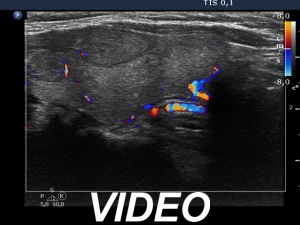

Ultrasonography. The thyroid was echonormal and hand numerous nodules. The nodule in the right side of the isthmus was the only one which increased over the last seven years.

Comment. It is worth analyzing the nodule in the right lobe which has echogenic granules. These figures are clearly back wall ones caused by posterior cystic enhancement.